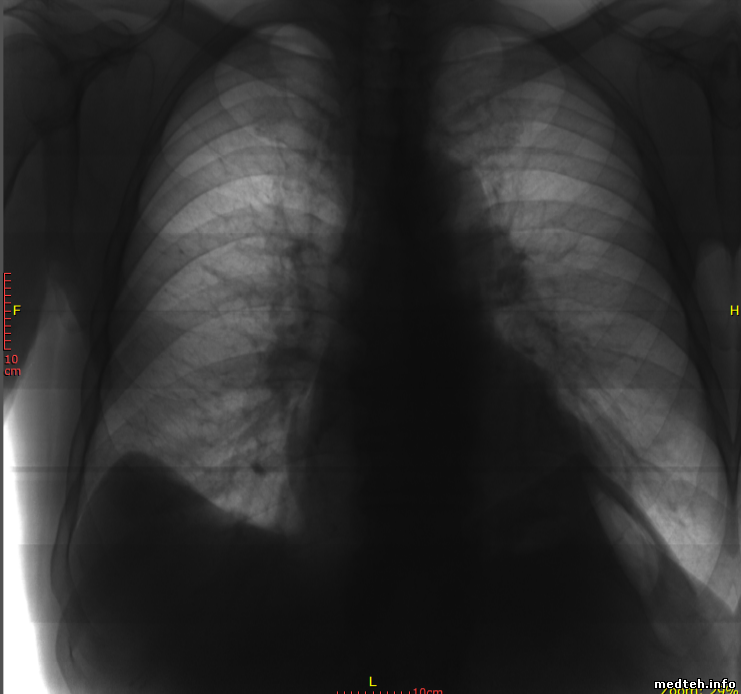

Здравствуйте! подскажите,аппарат проскан 2000 передвижной,перегнали из точки А в точку Б и после этого плохо снимает,на снимках зерно,говорят плата инвертора,может кто знает как исправить? Бутылки с водой снимает хорошо,а когда снимок человека,описание не сделать

Возможно. Но причины могут быть разные. Для начала сделай калибровку трубки и детектора. А вообще, не плохо бы увидеть снимок и желательно не на телефон с экрана.